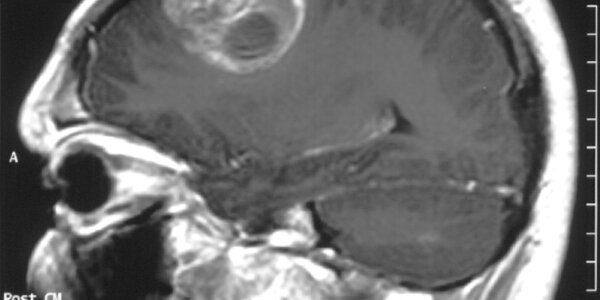

Introduction The most common form of  brain tumor in adults, glioblastoma multiforme (GBM), is not in fact a single disease but appears to be four distinct molecular subtypes, according to a study by The Cancer Genome Atlas (TCGA) Research Network. The researchers in this study also foundthat response to aggressive chemotherapy and radiation differed by subtype.The research team for TCGA is a collaborative effort funded by the National Cancer Institute (NCI) and the National Human Genome Research Institute (NHGRI), both parts of the National Institutes of Health. The Cancer Genome Atlas…

Cancer-initiating stem cells that launch glioblastoma multiforme, the most lethal type of brain tumor, also suppress an immune system attack on the disease, say scientists from The University of Texas M. D. Anderson Cancer Center. In a paper featured in the Jan. 15 issue of Clinical Cancer Research, the researchers demonstrate that this subset of tumor cells stifles the immune response in a variety of ways, but that the effect can be greatly diminished by encouraging the stem cells to differentiate into other types of brain cell. "We've known for years that glioblastoma and cancer patients…